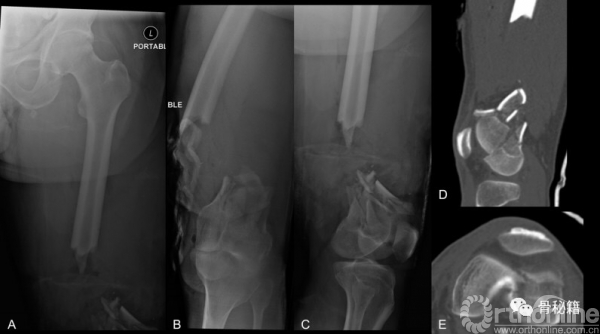

54岁男性,开放骨折,摩托车伤

股骨前方8X5cm的伤口,13-cm的骨缺损

股骨髁远端粉碎骨折

一期进行清创+外固定维持力线和长度+抗生素骨水泥

二期再次清创+骨水泥占位+远端拉力螺钉稳定关节面骨折块